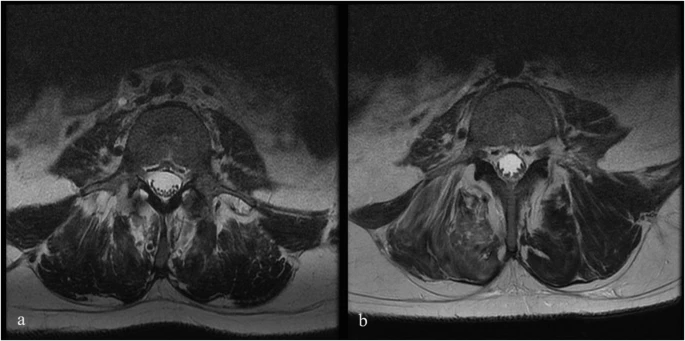

圖1:6號患者輸注前和輸注后MRI。

注射后血液和腦脊液檢查未發(fā)現(xiàn)異常。隨訪時MRI未見明顯變化;然而,在十名患者中,有八名檢測到馬尾神經(jīng)根的叢集輕度增加,有或沒有結(jié)節(jié)性增強的證據(jù)。在經(jīng)歷馬尾神經(jīng)根聚集或強化的患者中,沒有發(fā)現(xiàn)明顯的臨床相關(guān)性。圖1顯示了患者6的輸注前和隨訪MRI,該患者L4-S1水平的馬尾神經(jīng)根叢集輕度增加。表3突出顯示了所有患者干細胞注射前后的MRI變化。三名患者的SSEP有所改善。兩名患者與基線相比沒有任何變化,四名患者無法進行解釋,一名患者在整個研究期間具有正常的SSEP。表4突出顯示了SSEP 的發(fā)現(xiàn)和解釋。